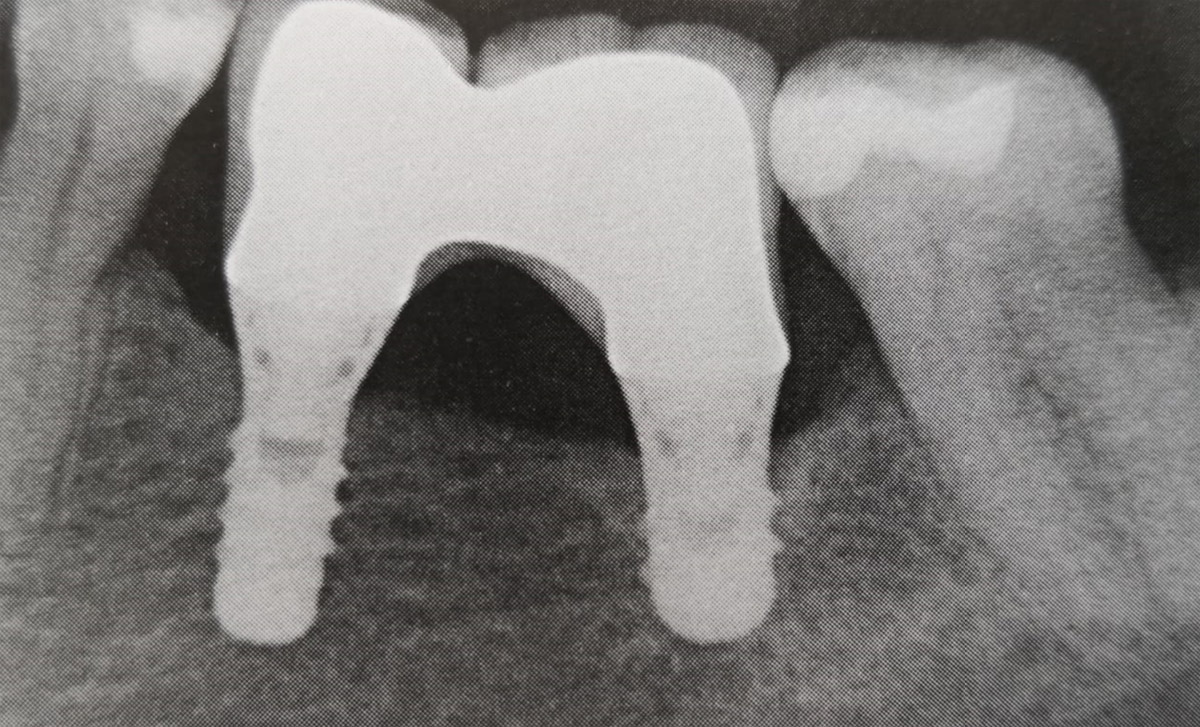

Impianti corti nei settori posteriori della mandibola senza rigenerazione ossea